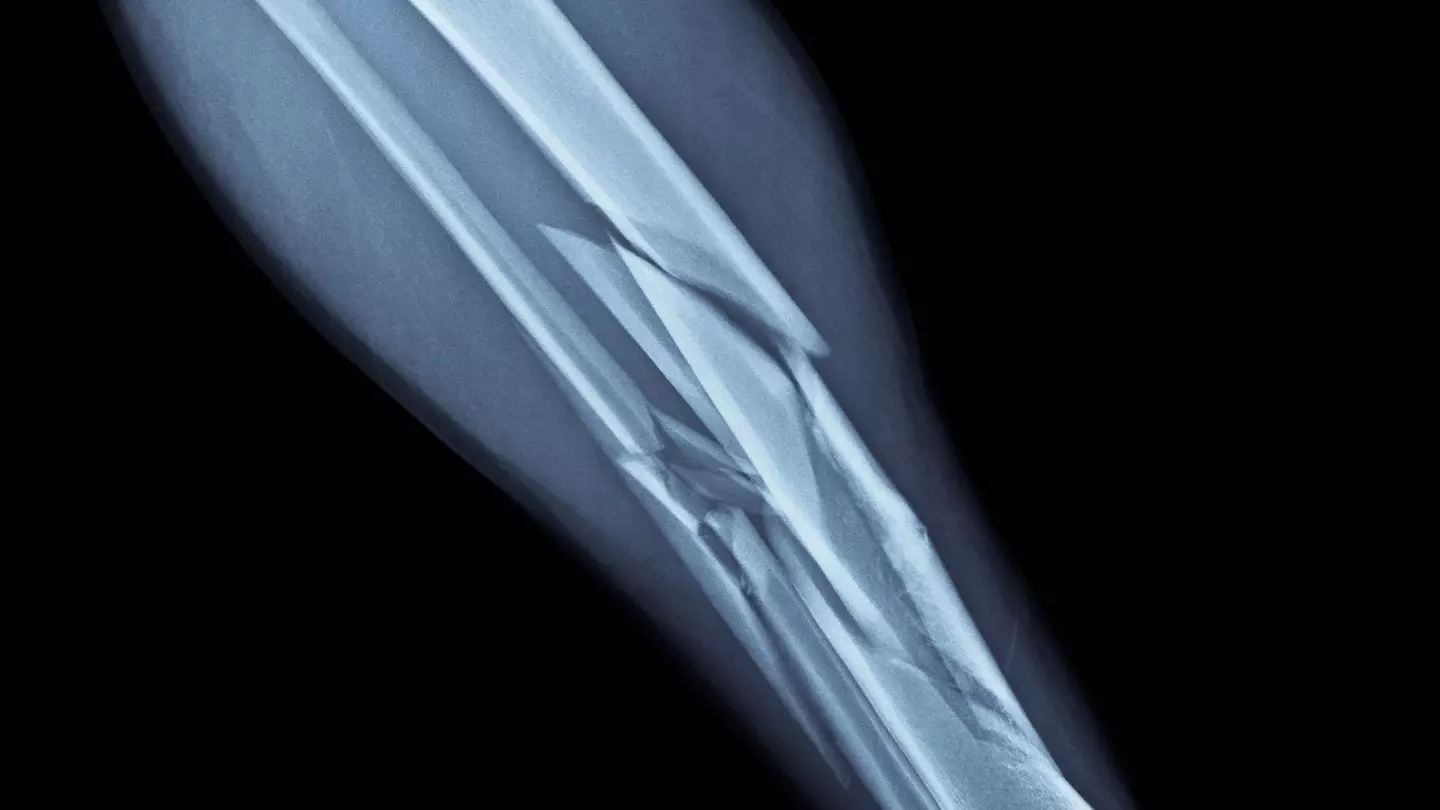

Broken bones are an unfortunate part of life and their isn't an age limit on them, but some lucky buggers manage to dodge them completely. They are often the result of clumsy accidents and traumatic falls, while people with underlying health conditions can be very susceptible to them too.

It turns out that the bones of a grown up are a lot more fragile than those of a small child, as adolescents boast a 'unique quality that allow their bones to heal faster'.

According to experts at Total Orthopaedic Care, a US firm who provide comprehensive orthopaedic and physical therapy services, adult bones can take months to mend themselves while kids can be back on their feet in just a matter of weeks.

"Unlike the bones in the adult body, the bones of children are still growing, so their growth pattern can more easily accommodate broken or fractured bones," it explains.

Anyway, the experts explain that kids have this superpower because the 'bones of a child contain far more periosteum, [which is] a dense layer of vascular connective tissue covering their bones'.

Total Orthopaedic Care notes: "Not only does this make their bones thicker and stronger, but it also means recovery and healing time is much quicker.

"This is because the bones are far more oxygen-rich, allowing it to more easily heal after trauma.

"However, due to the incredible thickness in children’s bones, it makes it significantly more difficult to diagnose small fractures. So, if your child is complaining of pain after an accident or fall, you should be quick to get medical attention."

It's also worth mentioning that children typically experience broken bones due to unexpected 'trauma or sports injuries' whereas adults are 'more susceptible to wear-and-tear types of fractures'.

"This is when cartilage and bones break down over time – as can happen with arthritis or osteoporosis – leading to bones breaking more easily with a fall," Total Orthopaedic Care adds.